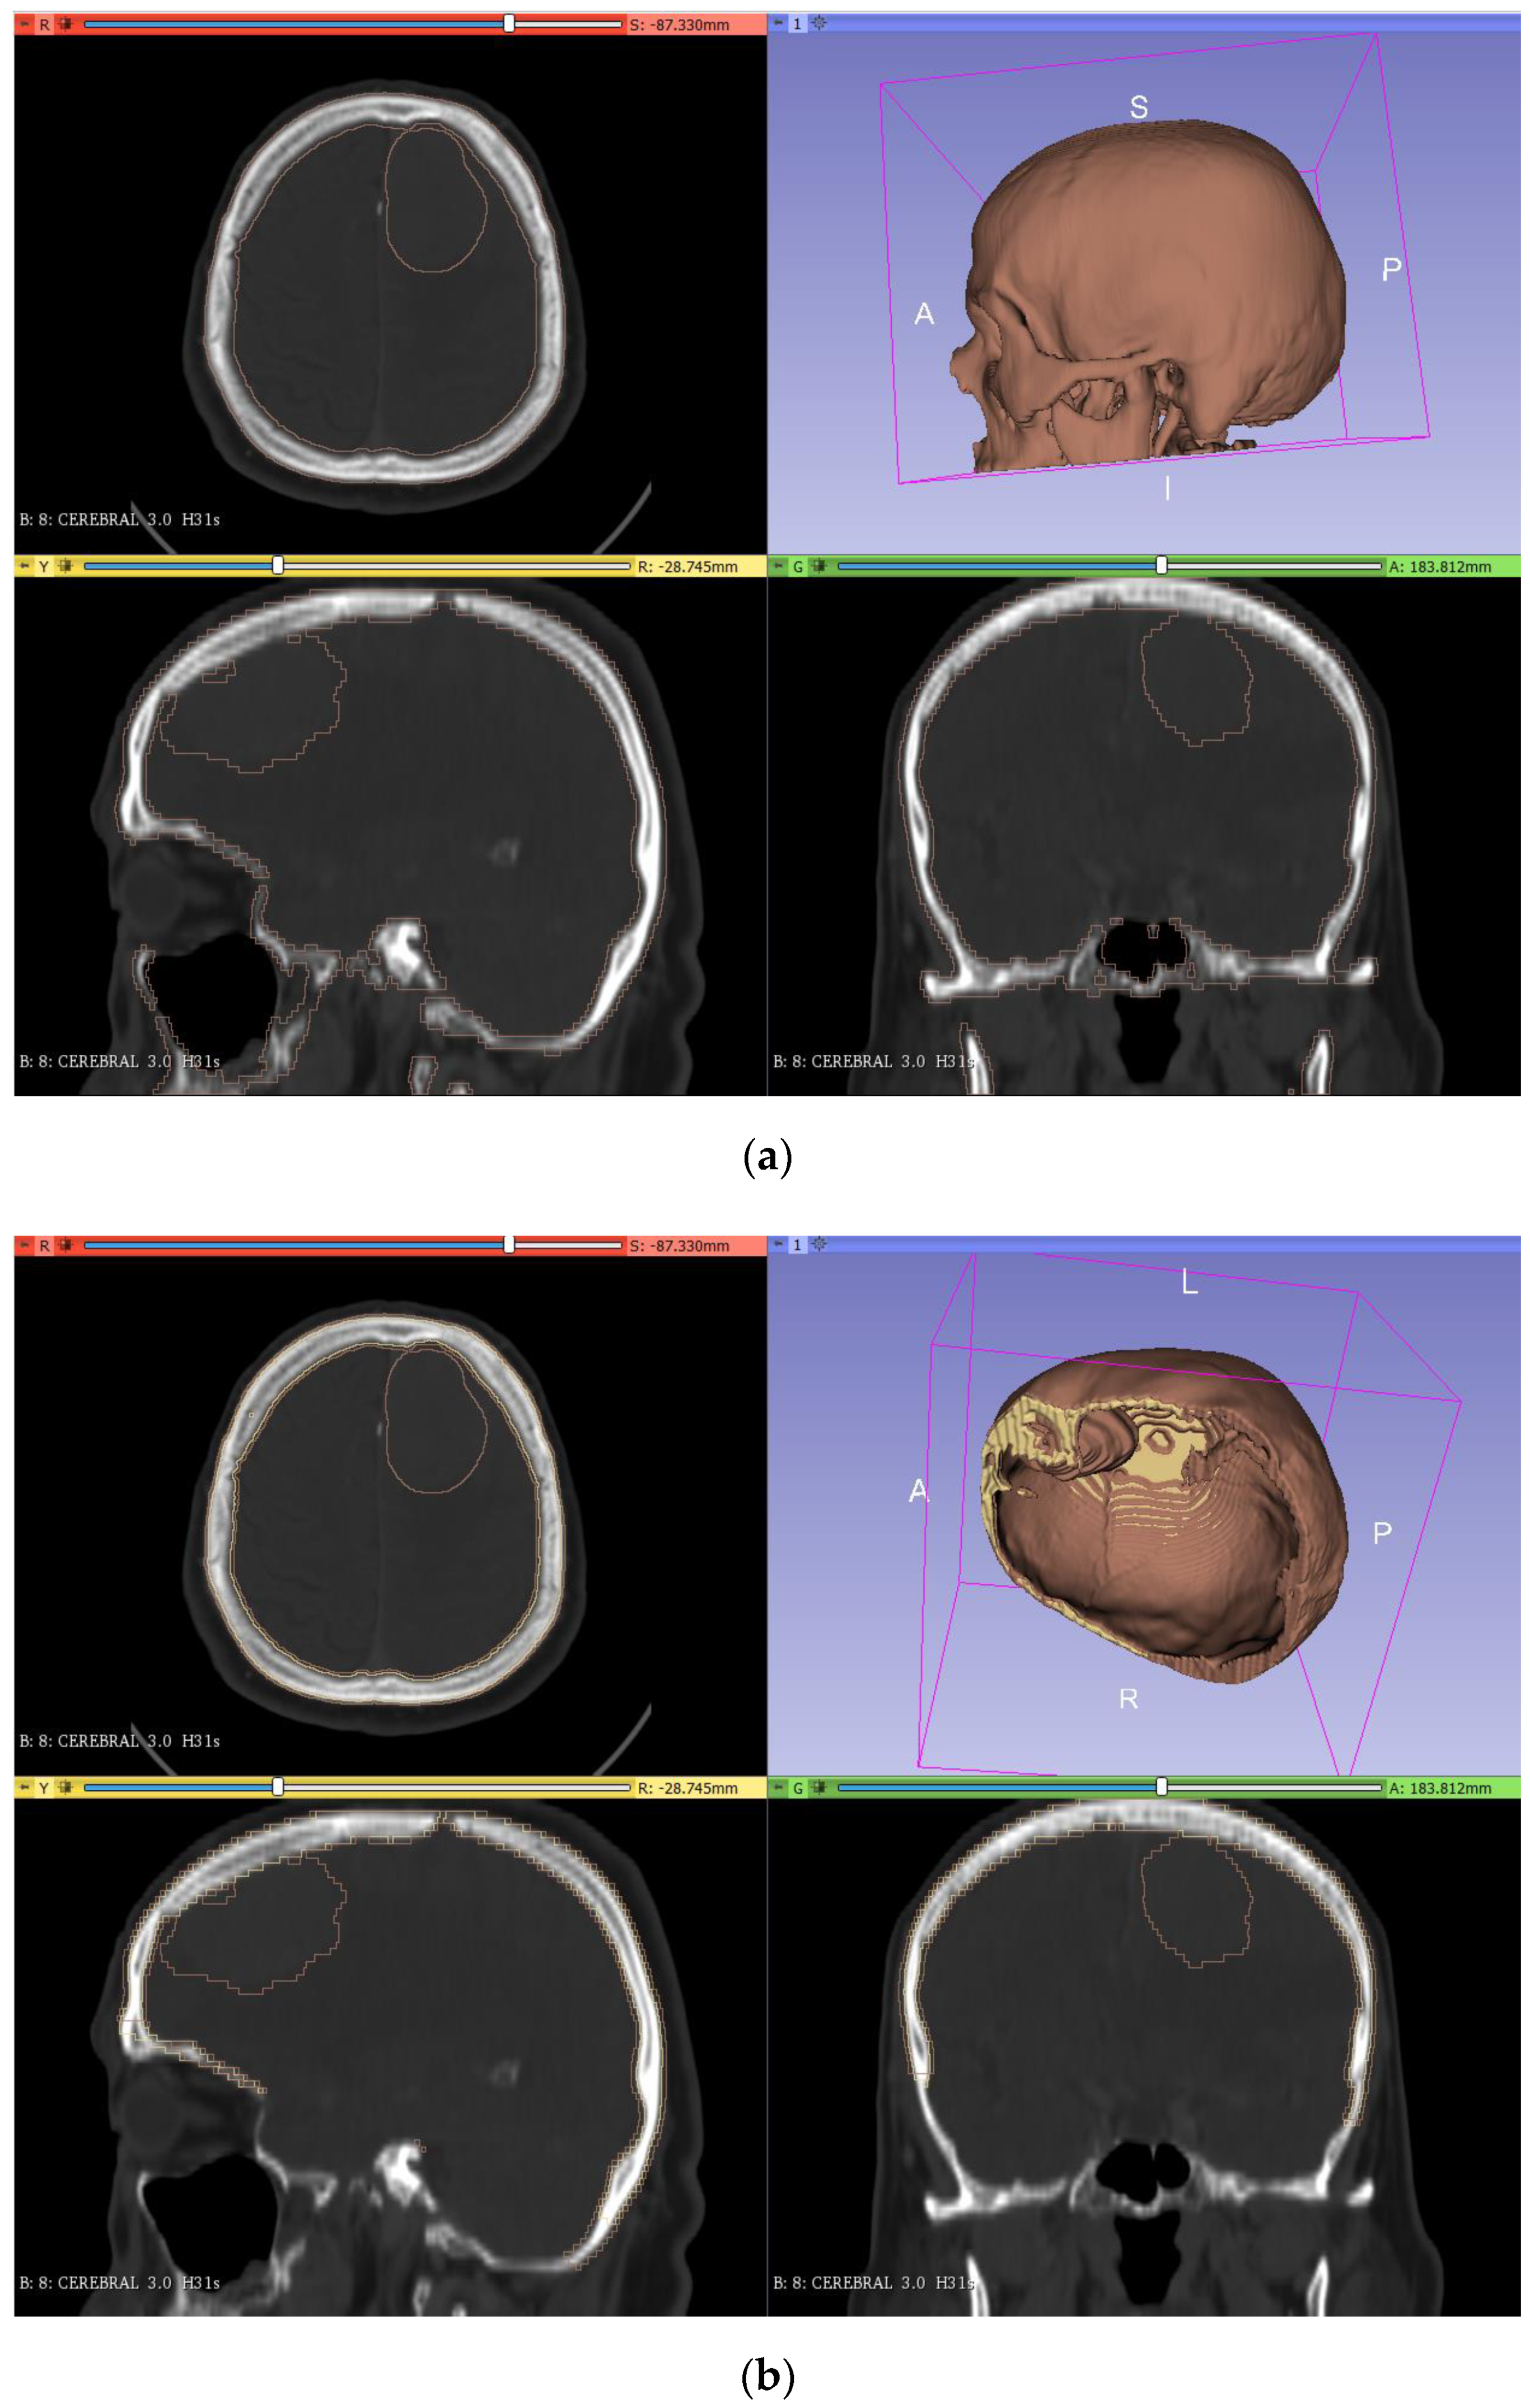

To obtain the final model of the skull, we performed the segmentation (Figure 2a) and cutting (Figure 2b) with the different 3DSlicer tools. For the segmentation step, the ‘threshold’ tool (in the segment editor) was used, adjusting the range values until the selected pixels matched the zone of the bone. After this, the cutting of the lower part of the bone was carried out by using the ‘scissors’ tool. Finally, the resulting model was saved as an STL file and converted into a solid STL file in the Meshmixer software (‘make solid’ tool, in the ‘edit’ menu).

Figure 2.

Segmentation (a) and cutting (b) of the skull model from the DICOM images in 3DSlicer.

As mentioned above, the production of a tumor prototype requires a mold where the silicone mixture has to be poured to obtain the desired geometric model. To do this, the model was segmented (Figure 3a) using a similar approach to that applied for the bone segmentation. However, since the tumor is not easily differentiated from the brain, more manual work was needed. The first step was to apply the ‘threshold’ tool in the segment editor to try to select all the pixels corresponding to the tumor by adjusting the range of application. As the previous step was not accurate due to the color similarity between the brain and tumor, the ‘erase’ and ‘paint’ tools were used, layer by layer, to adjust the segmented area (‘erase’ to remove areas and ‘paint’ to add new areas to the segment). After this, a copy of the segmented model was made (‘logical operators’, ‘copy’ operation) with an added thickness of 10 mm (‘margin’ tool). Then, the original model was subtracted to the increased model (‘logical operators’ tool, ‘subtract’ operation), leaving a hollow segmented model as a mold (Figure 3b).

Figure 3.

Segmentation (a) and creation of the tumor mold (b) from the DICOM images in 3DSlicer.

2.2.3. Brain Mold

In the making of the mold of the brain, the first step was to join the segmented model of the skull and the tumor (in the segment editor, ‘logical operators’ tool, ‘add’ operation) so that this mold had the shape of the tumor inside (Figure 4a). Then, the thickness was increased by 3 mm (‘margin’ tool) so that the molded brain had 3 mm of clearance with the skull. Finally, the model was cut (‘scissors’ tool) following the same plane as in the skull cutting (Figure 4b).

Figure 4.

Segmentation (a) and creation of the brain mold (b) from the DICOM images in 3DSlicer.